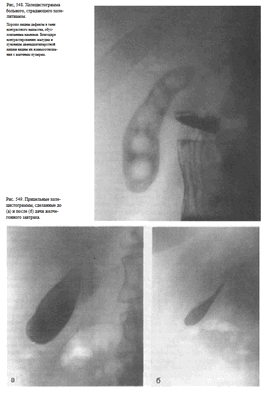

Информативность снимка. На обзорной рентгенограмме (электро-рентгенограмме) живота отображаются очертания печени, почек, больших поясничных мышц, желудка и кишечника (при наличии в них газа), а также диафрагма, вход в малый таз и боковые каналы брюшной полости (рис. 538).

На обзорных снимках живота, выполненных в положении больного стоя или сидя, хорошо видны раздутые газом кишечные петли с уровнями жидкости при кишечной непроходимости

Информативность снимке. На латерограмме отображаются преимущественно правая половина живота и расположенные здесь органы. Особенно отчетливо при этом виден свободный газ в брюшной полости (рис. 543).

На снимке, выполненном в положении больного на спине, при перфорации полого органа под передней брюшной стенкой определяется свободный газ (рис. 545).